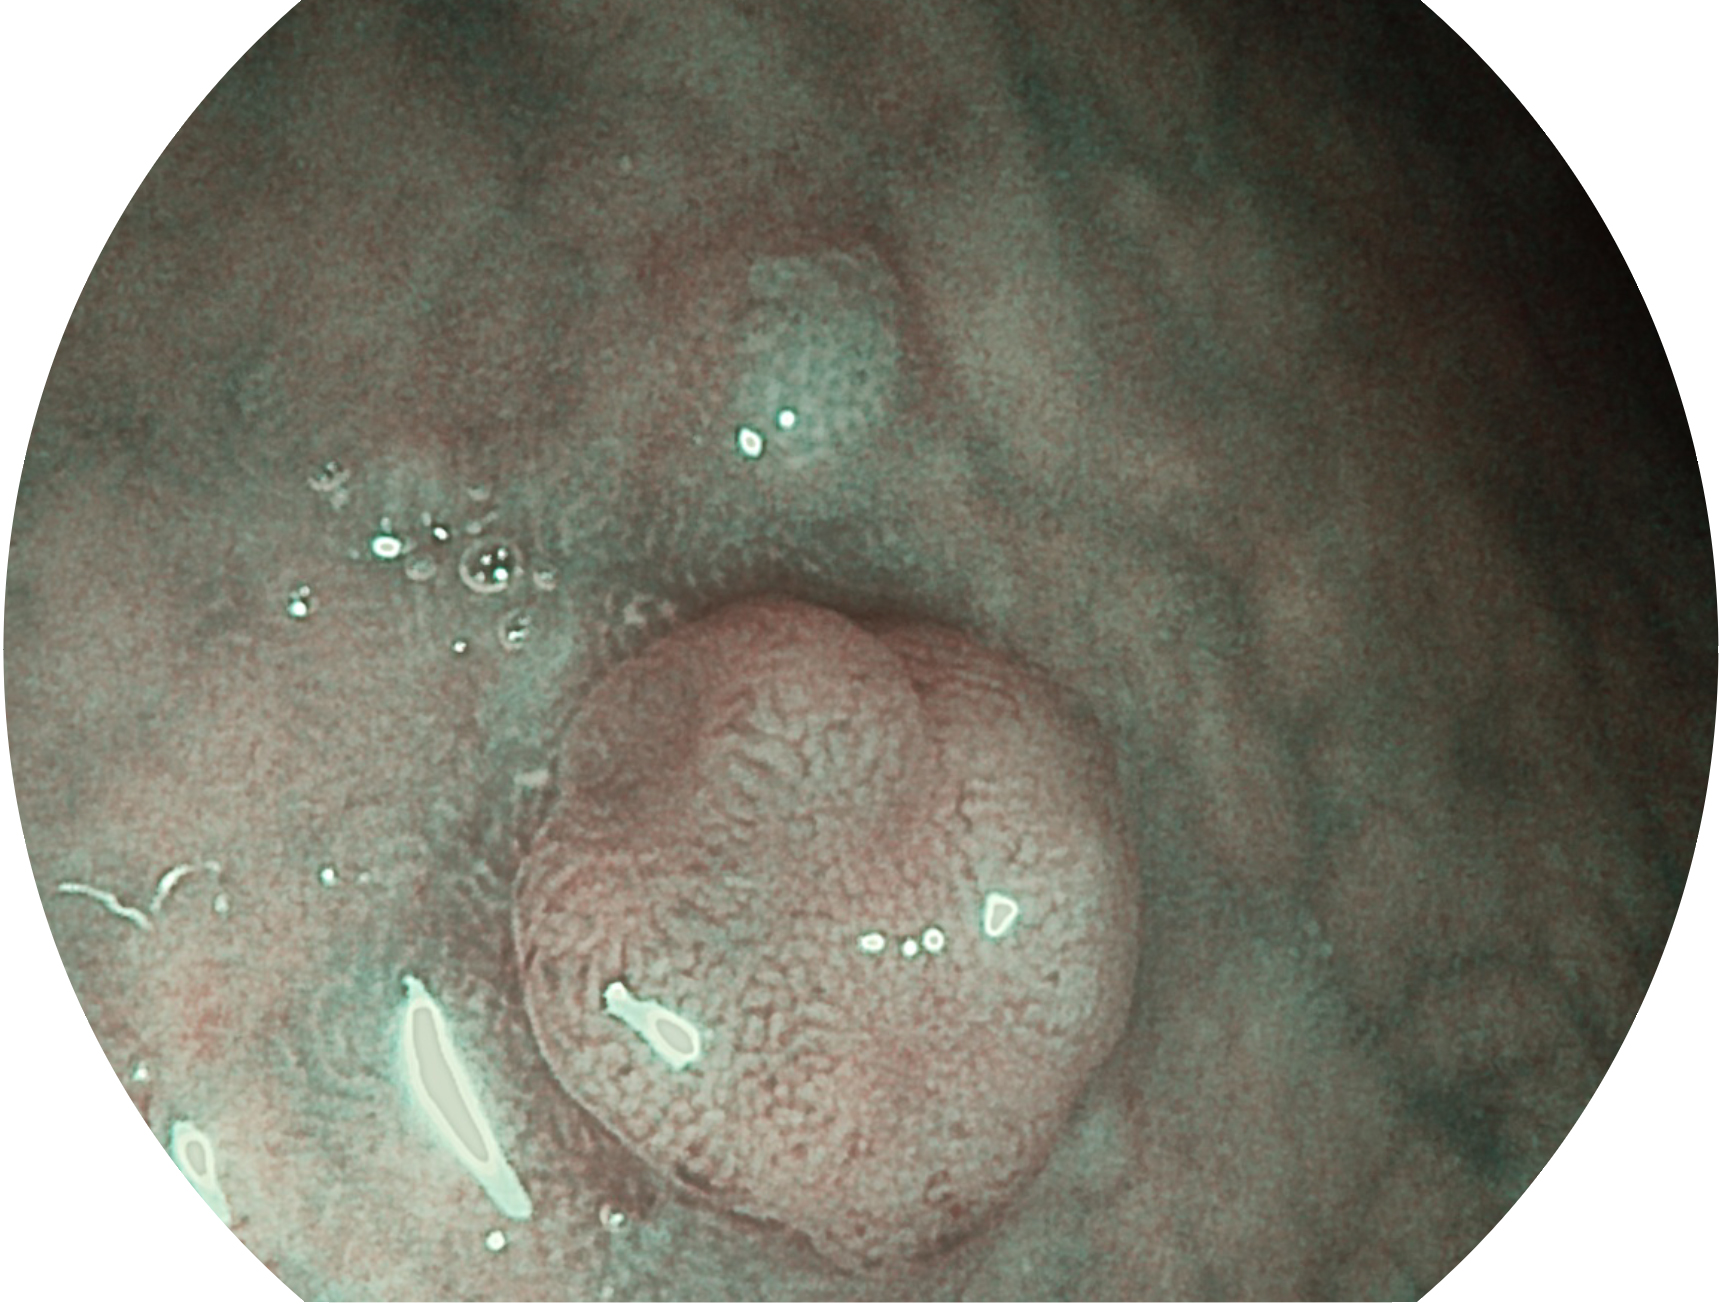

玖鼎集团新开发的内镜染色技术,主要是基于多波长LED 光源的开发,VLS-55Q 四波长LED 光源是由四个不同颜色的LED光按照相应照明模式所规定的特定发光比例进行合束后形成,合束后形成的照明光的光谱由红光、绿光、蓝光及蓝紫光这四个不同的波段范围构成。具有更高光谱自由度,通过光谱比例的控制,实现了聚谱成像技术,英文全称为“Spectral Focused Imaging, SFI”,缩写为“SFI”和光电复合染色成像技术,英文全称为“Versatile Intelligent Staining Technology, VIST”,缩写为“VIST”。